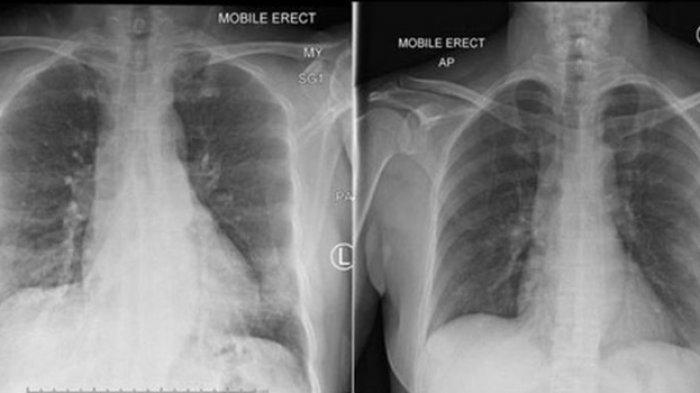

Peneliti China telah menemukan kantung berisi cairan atau serpihan di paru-paru pasien yang terinfeksi Virus Corona.

Hasil pemindaian menunjukkan bahwa mereka yang sembuh dari Virus Corona bisa mengalami penurunan fungsi paru-paru.